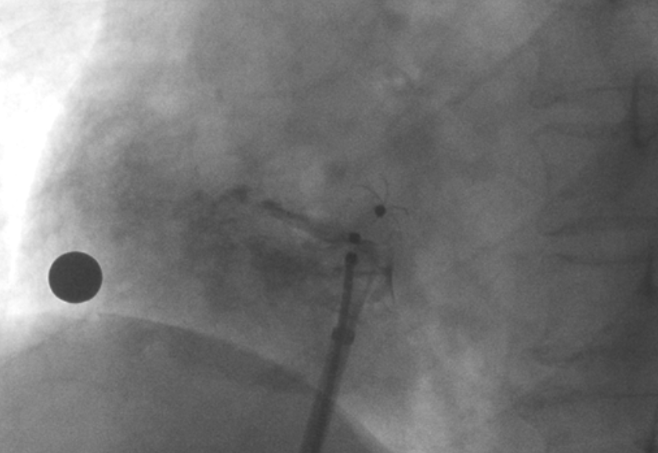

術(shù)中造影顯示患者為PFO且長(zhǎng)隧道型,目前市場(chǎng)上已商業(yè)化的PFO封堵器難以滿足該患者解剖結(jié)構(gòu)封堵需求。迪創(chuàng)醫(yī)療自主研發(fā)的OmniSeal PFO封堵器自適應(yīng)性雙盤貼合設(shè)計(jì)能廣泛適應(yīng)不同PFO隧道長(zhǎng)度的解剖結(jié)構(gòu)和形態(tài),其雙盤外包覆式阻流和隧道內(nèi)填充阻流相結(jié)合的雙重阻流設(shè)計(jì),可為此患者實(shí)現(xiàn)有效封堵。與此同時(shí),OmniSeal首創(chuàng)的完全可穿刺式設(shè)計(jì),也為此患者最大程度地保留了房間隔區(qū)域穿刺通道,以實(shí)現(xiàn)全兼容未來可能的左心系統(tǒng)二次介入術(shù)。術(shù)終造影和心臟超聲顯示封堵完全、效果良好。作為OmniSeal的首例臨床應(yīng)用,本次手術(shù)的順利完成和優(yōu)異效果充分體現(xiàn)了產(chǎn)品的設(shè)計(jì)創(chuàng)新優(yōu)勢(shì)。

造影顯示PFO封堵完全,無殘余分流, 試驗(yàn)器械充分舒展并貼合良好